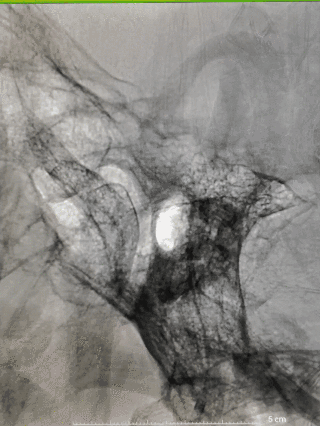

手术过程

图4右颈内动脉海绵窦段起始部类圆形瘤样扩张,最大约19mm╳14mm,瘤颈约14mm,瘤内射流明显,载瘤动脉远端5mm,近端4.5mm。

8F常规指引到右颈内动脉开口做近端支撑。Synchro 0.014 200微导丝及XT-27微导管引导CAT 5导管同轴越过右颈内动脉瘤至右大脑中动脉M1。由于动脉瘤颈较大,微导丝引导XT-27微导管,无法直接通过,采用瘤内成袢技术通过。选取Surpass Streamline 5mm╳30mm经CAT 5导管释放,并行微导丝及CAT 5导管按摩。

图5